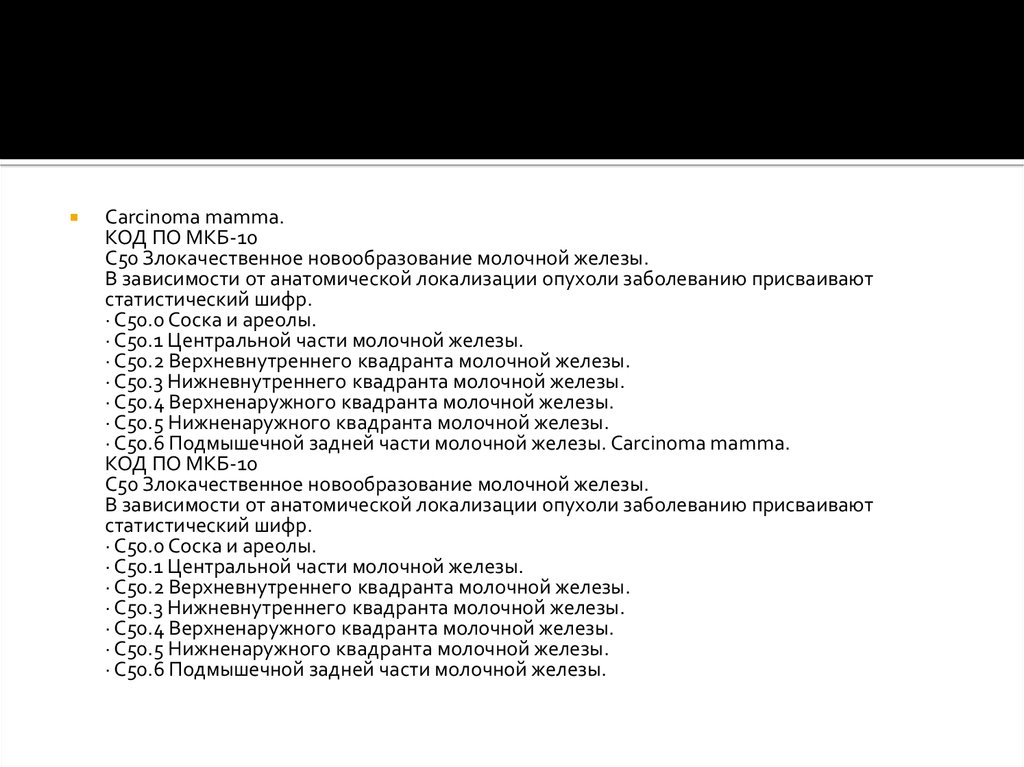

Код мкб 10 атерома головы

Код мкб 10 атерома головы 109 фото